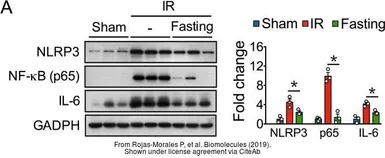

The data was published in the journal Biomolecules in 2019. PMID: 31505885